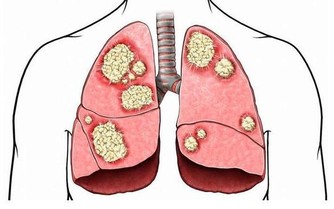

他進一步說明道,長期服用恐增加心血管疾病與乳癌發生風險的為傳統荷爾蒙治療,

但目前更年期治療多是採用新一代「類荷爾蒙」治療,可以改善症狀,又不過度刺激乳房與子宮內膜,